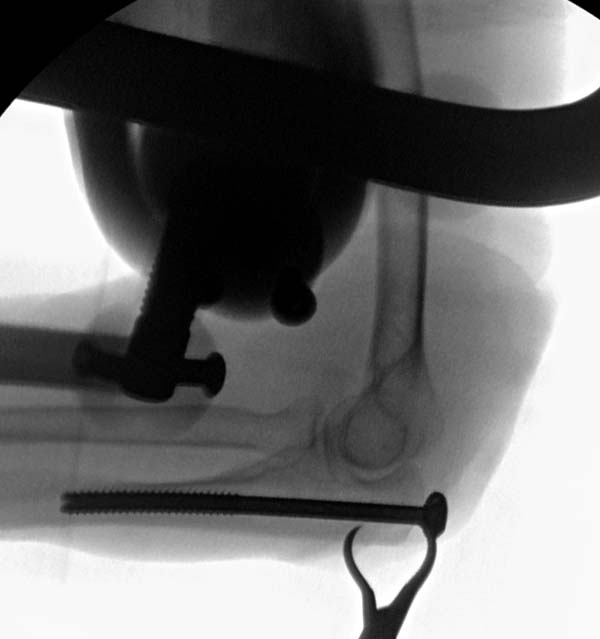

Первоначально на клиническом разборе планировалась костная аутопластика с фиксацией пластинкой или аппаратом внешней фиксации. Однако в течение нескольких дней у больной систематически отмечался подъем АД до 200-220 мм.рт.ст., трудно снимаемый гипотензивной терапией, назначенной по рекомендации терапевта. Через 1 неделю п/травмы больная взята в операционную и … снята со стола с очередным гипертоническим кризом (АД 230/100 мм.рт.ст.). Подключена терапия, на этот раз назначенная кардиологом. Повторное обсуждение случая с врачами отделения. Предложения: или от операции отказаться, или выполнить остеосинтез локтевого отростка, в любом случае - без наркоза. Учитывая «злокачественное» течение гипертонической болезни с исключительно лабильной гемодинамикой в ответ на малейшее эмоциональное волнение пациентки, решено выполнить остеосинтез спицами с проволочной петлей и костной аутотрансплантацией из дистального отломка локтевой кости (из этого же оперативного доступа) под проводниковой анестезией. АД удалось стабилизировать за 2 дня до операции. Через 2 недели после травмы больная вновь взята в операционную. Выполнена верхняя проводниковая анестезия по Соколовскому. Непосредственно перед началом операции на операционном столе у больной опять отмечен подъем АД до 190 мм.рт. ст. . В течение 30 минут анестезиологом проводилась коррекция АД и с давлением 150 мм.рт.ст. операция начата. После выполнения заднего доступа по Фарабефу обнажена зона перелома. Выявлен раздробленный перелом локтевого отростка с множеством промежуточных мелких костных фрагментов и отсутствием губчатой кости (остеопороз), проксимальный отломок представлен 3 –мя отломками размером 1-1,5см каждый, местами связанных между собой надкостницей. В момент ревизии костных отломков АД упало до 100/60 мм.рт. ст. Решено отказаться от выполнения костной аутопластики, и как можно быстрее заканчивать операцию. Произведен остеосинтез локтевого отростка двумя спицами и проволочной петлей, при этом обнаружено, что малейшее стягивание петли, проведенной в виде «обычной восьмерки» ведет к деформации локтевого отростка за счет компрессии (сминания) промежуточных фрагментов. В связи с этим спицы проведены перекрестно друг к другу, а проволока закручена вокруг выстоящих концов спиц (для увеличения стабильности проксимальных отломков), при этом закрученные концы ее не скушены, а уложены вдоль локтевого отростка для предупреждения вторичного смещения промежуточных фрагментов. Продолжительность операции – 35 минут. На контрольных рентгенограммах (доставленных в операционную уже после ушивания раны) – отломки в положении контакта, положение костных отломков локтевой кости удовлетворительное (см. фото 3,4). Гипсовая иммобилизация не проводилась. Правая верхняя конечность подвешена в косыночной повязке.